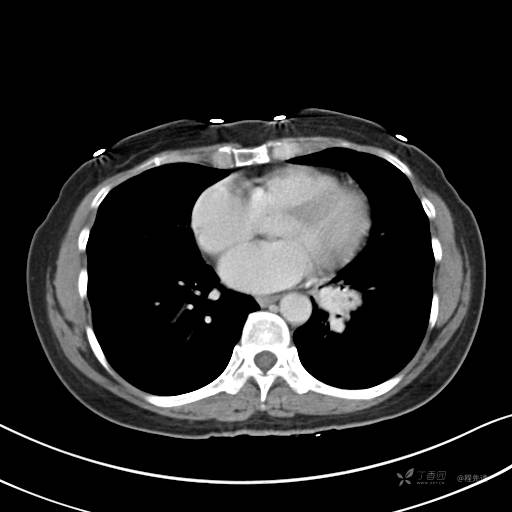

增强静脉期

静脉期CT值约84HU